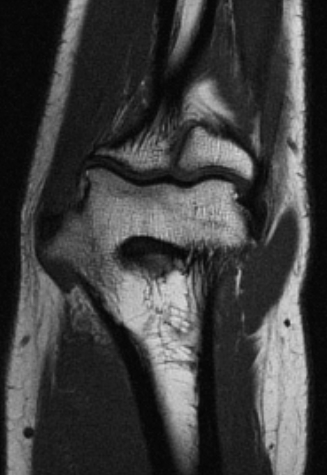

La Resonancia magnética (RMN) es un método de imagen multiplanar no invasivo, basado en la interacción entre la radiofrecuencia, los campos magnéticos y ciertos núcleos en el cuerpo humano (generalmente núcleos de hidrógeno del agua), después que el cuerpo ha sido introducido en un campo magnético fuerte. La información obtenida es procesada por un ordenador y transformada en imágenes del cuerpo humano.

La RM consigue información sobre la estructura del cuerpo permitiendo diferenciar entre tejidos normales y anormales lo que la convierte en una técnica muy sensible para detectar enfermedad. Esta sensibilidad está basada en un alto grado de contraste debido a las variaciones en las propiedades de relajación magnética de los diferentes tejidos, tanto normales como anormales.